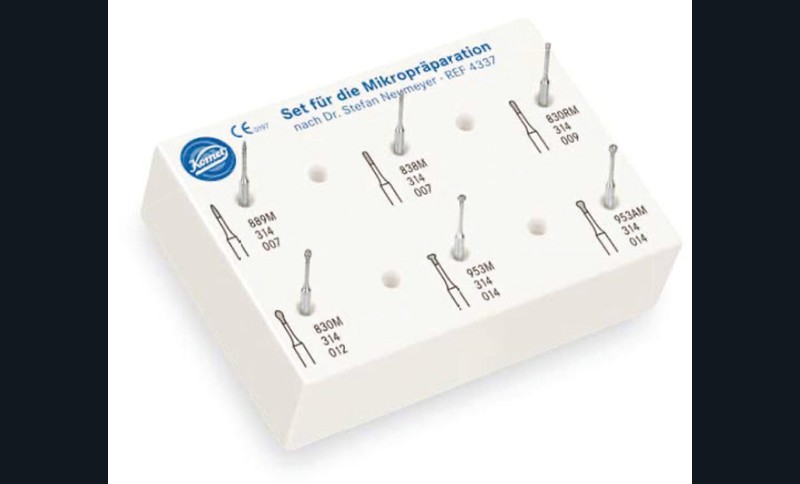

- soit de façon invasive a minima. Cette économie tissulaire peut se faire notamment avec l’utilisation de fraises adaptées et minimalement invasives (fig. 4).

• Traitement invasif a minima : il concerne les lésions carieuses cavitaires ou non avec atteinte dentinaire (à partir du 1/3 moyen dentinaire), soit ICDAS 3 à 6. Dans ce cas, la priorité est de préserver la dent d’une effraction pulpaire éventuelle (recommandations de l’ESE) [4]. C’est pourquoi, lors du traitement de lésions carieuses profondes (ICDAS 4 à 6), il faut dans tous les cas réaliser une éviction sélective, réaliser une préparation a minima (favoriser les préparations de type fente (« slot ») ou tunnel lorsque l’indication se pose) et utiliser un matériau de restauration de choix, soit composite, soit un ciment verre ionomère (CVI), soit des matériaux à base de silicate de calcium ou encore les nouveaux composites enrichis en minéraux (fig. 7 à 9). Ces préparations a minima peuvent être réalisées avec des fraises de petits diamètres (fig. 10 et 11).